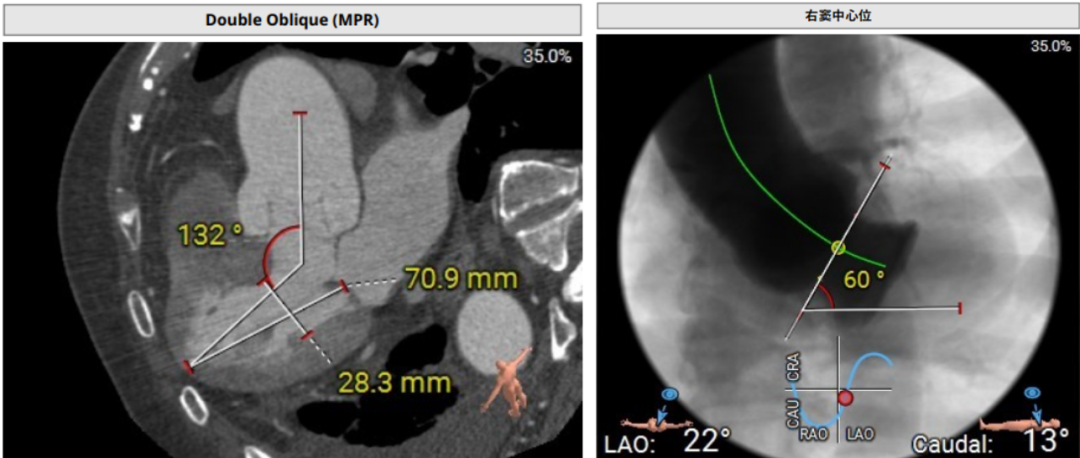

术前超声和DSA评估提示,患者三叶瓣结构,三个瓣窦,三窦偏大。主动脉瓣环30.1mm,左心室流出道直径28.1mm,STJ直径43.9mm,升主动脉直径47.4mm,左侧冠脉高度23.3mm,右侧冠脉高度22.3mm,左室-主动脉夹角132°。